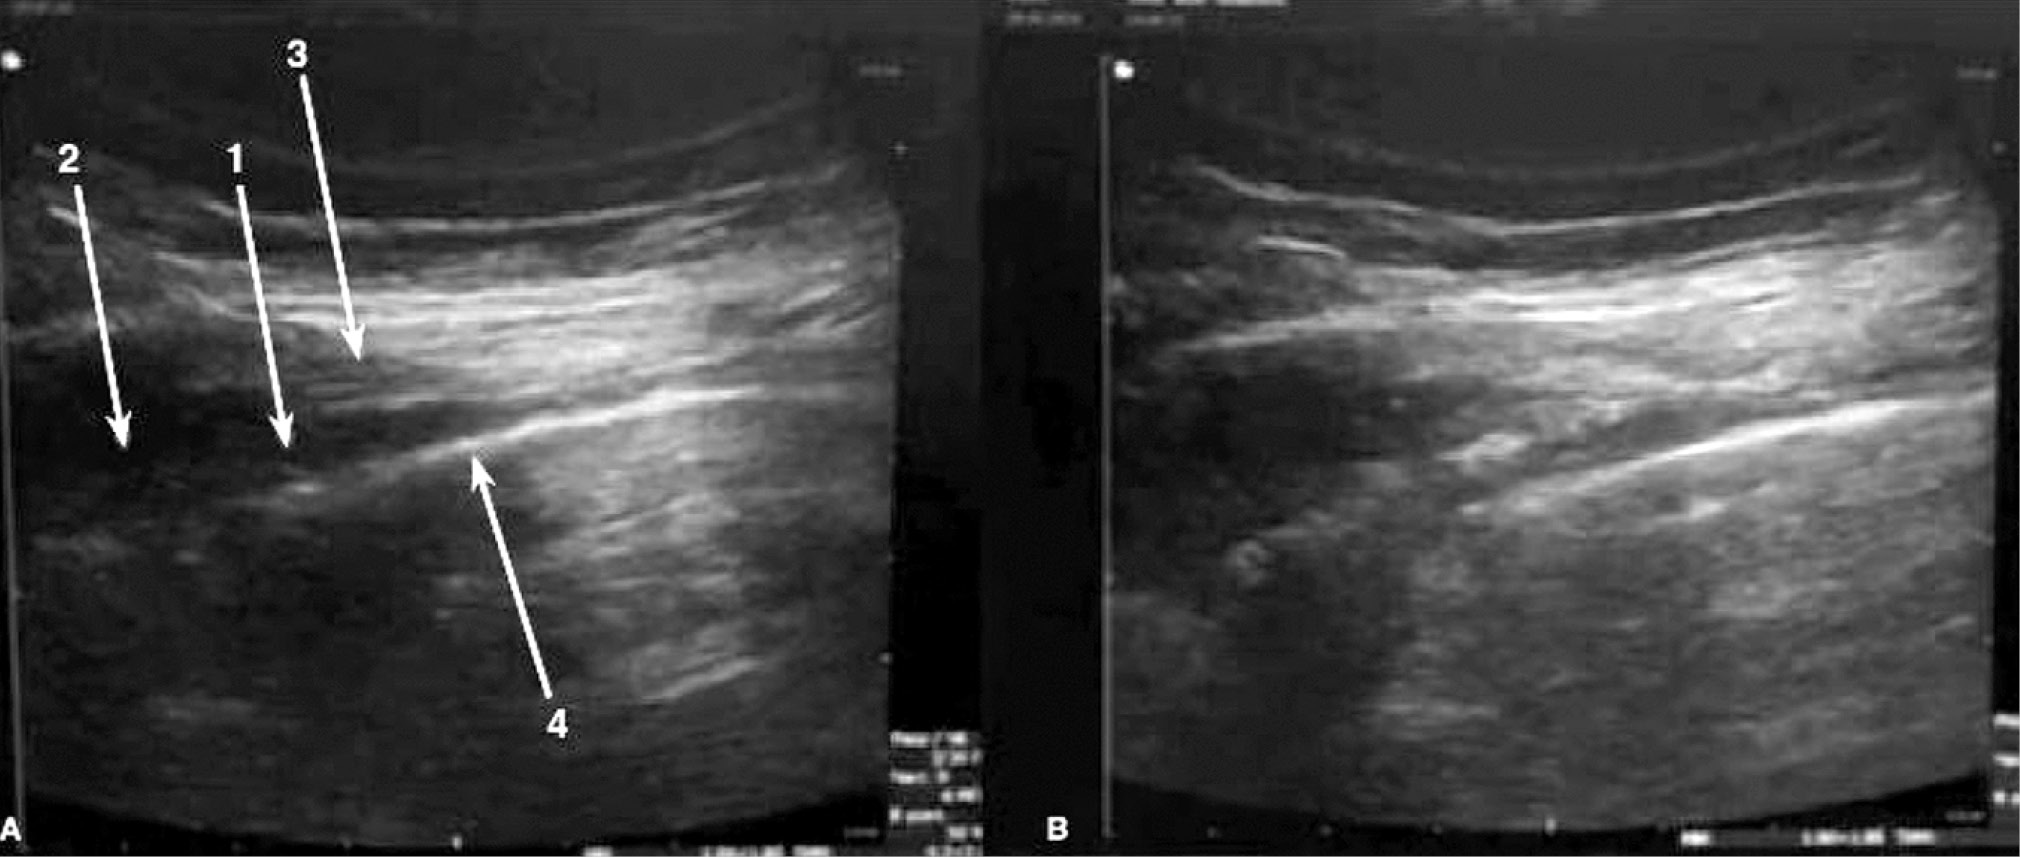

Техника паравертебральной блокады заключается во введении местного анестетика (ропивакаин, бупивакаин) в паравертебральное пространство (ПВП) – анатомическое образование треугольной формы, ограниченное париетальной плеврой спереди, телом позвонка медиально, поперечным отростком и поперечно-рёберной связкой сзади (см. рис.).

Рис. Введение анестетика в паравертебральное пространство. А) 1 – паравертебральное пространство, 2 – тело позвонка, 3 – поперечно-рёберная связка, 4 – париетальная плевра. B) визуализировано расширение паравертебрального пространства, свидетельствующее об успешном введении препарата / Fig. Injection of an anesthetic into the paravertebral space. A) 1 – paravertebral space, 2 – vertebral body, 3 – transverse costal ligament, 4 – parietal pleura. B) Expansion of the paravertebral space is visualized, indicating successful administration of the drug

После введения анестетика в паравертебральное пространство блокируются задние ветви спинномозговых нервов, белые и серые коммуникантные ветви, а также симпатическая цепочка, что обеспечивает как эфферентную, так и афферентную блокаду проводимости нервных волокон ещё до входа в спинной мозг. Существуют 4 вида ПВБ в зависимости от анатомической области, которую необходимо обезболить: шейная, грудная, тораколюмбальная и поясничная. ПВП сообщается с эпидуральным пространством (через межпозвоночные отверстия) и таким же отделом с противоположной стороны (через эпидуральное и превертебральное пространство) [15, 16]. Грудной отдел ПВП также сообщается с межрёберными пространствами, а грудной и поясничный отделы паравертебрального пространства – с поперечным пространством живота [17–19]. В ПВП находятся межрёберные сосуды и жировая клетчатка, а также спинальные нервы, которые делятся на вентральные и дорзальные ветви, симпатический ствол, белые и серые соединительные ветви симпатического ствола [19–21]. В этой анатомической области спинальные нервы не покрыты эпиневрием, а нервные фасцикулы имеют тонкий слой периневрия, поэтому раствор местного анестетика легко проникает к проводящим волокнам и вызывает их блокаду [19, 22, 23].

Существует несколько различных методик проведения ПВБ. Слепая методика заключается в проведении иглы до поперечного отростка позвонка на расстоянии 2–3 см от срединной линии, последующем обхождении его (снизу или сверху), последующем присоединении шприца потери сопротивления, и в момент потери сопротивления – введении анестетика в паравертебральное пространство. Также возможно проведение иглы после контакта с поперечным отростком на заранее рассчитанное расстояние (равное 1,5–2 см у взрослых) для попадания в паравертебральное пространство. Объективизировать проведение ПВБ можно и с помощью нейростимулятора. При проведении ПВБ по описанной выше слепой методике, но с применением изолированной иглы и нейростимулятора, при наличии моторного ответа соответствующих мышц передней брюшной стенки при силе тока 0,2–0,4 мA, можно быть уверенным, что кончик иглы находится в ПВП, и ввести местный анестетик. Наиболее точной методикой среди представленных является проведение ПВБ под ультразвуковым (УЗИ) наведением. Использование ультразвукового датчика позволяет визуализировать анатомические структуры, служащие ориентирами, а также увидеть распространение местного анестетика в паравертебральном пространстве. Признаком правильности проведения блокады является отслойка и вентральное движение париетальной плевры при введении местного анестетика. Частота удачных блокад при данной методике крайне высока и в некоторых исследованиях достигает 100% [24].